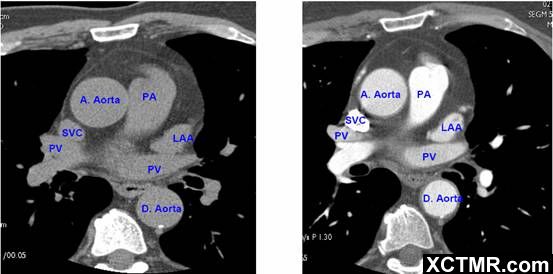

常用英文名称及缩写 LA - Left Atrium 左心房 RA - Right Atrium 右心房 LV - Left Ventricle 左心室 RV - Right Ventricle 右心室 Mitral Valve 二尖瓣 A. Aorta-Ascending Aorta 升主动脉 D. Aorta-Descending Aorta 降主动脉 SVC – Superior Vena Cava 上腔静脉 IVC – Inferior Vena Cava 下腔静脉 PA - Pulmonary Artery 肺动脉 PV - Pulmonary Vein 肺静脉 LMA - Left Main Artery 冠状动脉左主干 LAD - Left Anterior Descending Artery 左前降支 LCX - Left Circumflex Artery 左回旋支 LMB - Left Obtuse Marginal Branch 左边缘支(钝缘支) RCA - Right Coronary Artery 右冠状动脉 PDA - Posterior Descending Artery 后降支 Conus Branch 右动脉圆锥支 LAA – Left Atrial Appendage 左心耳 RAA – Right Atrial Appendage 右心耳 CS - Coronary Sinus 冠状窦 MCV – Middle Cardiac Vein 心中静脉 GCV –Great Cardiac Vein 心大静脉 PIVV – Posterior Intraventricular Vein 后室间静脉(心中静脉) PLVV – Posterior Left Ventricular Vein 左室后静脉 PLV – Posterior Lateral Vein 左室后侧静脉(边缘静脉) | |